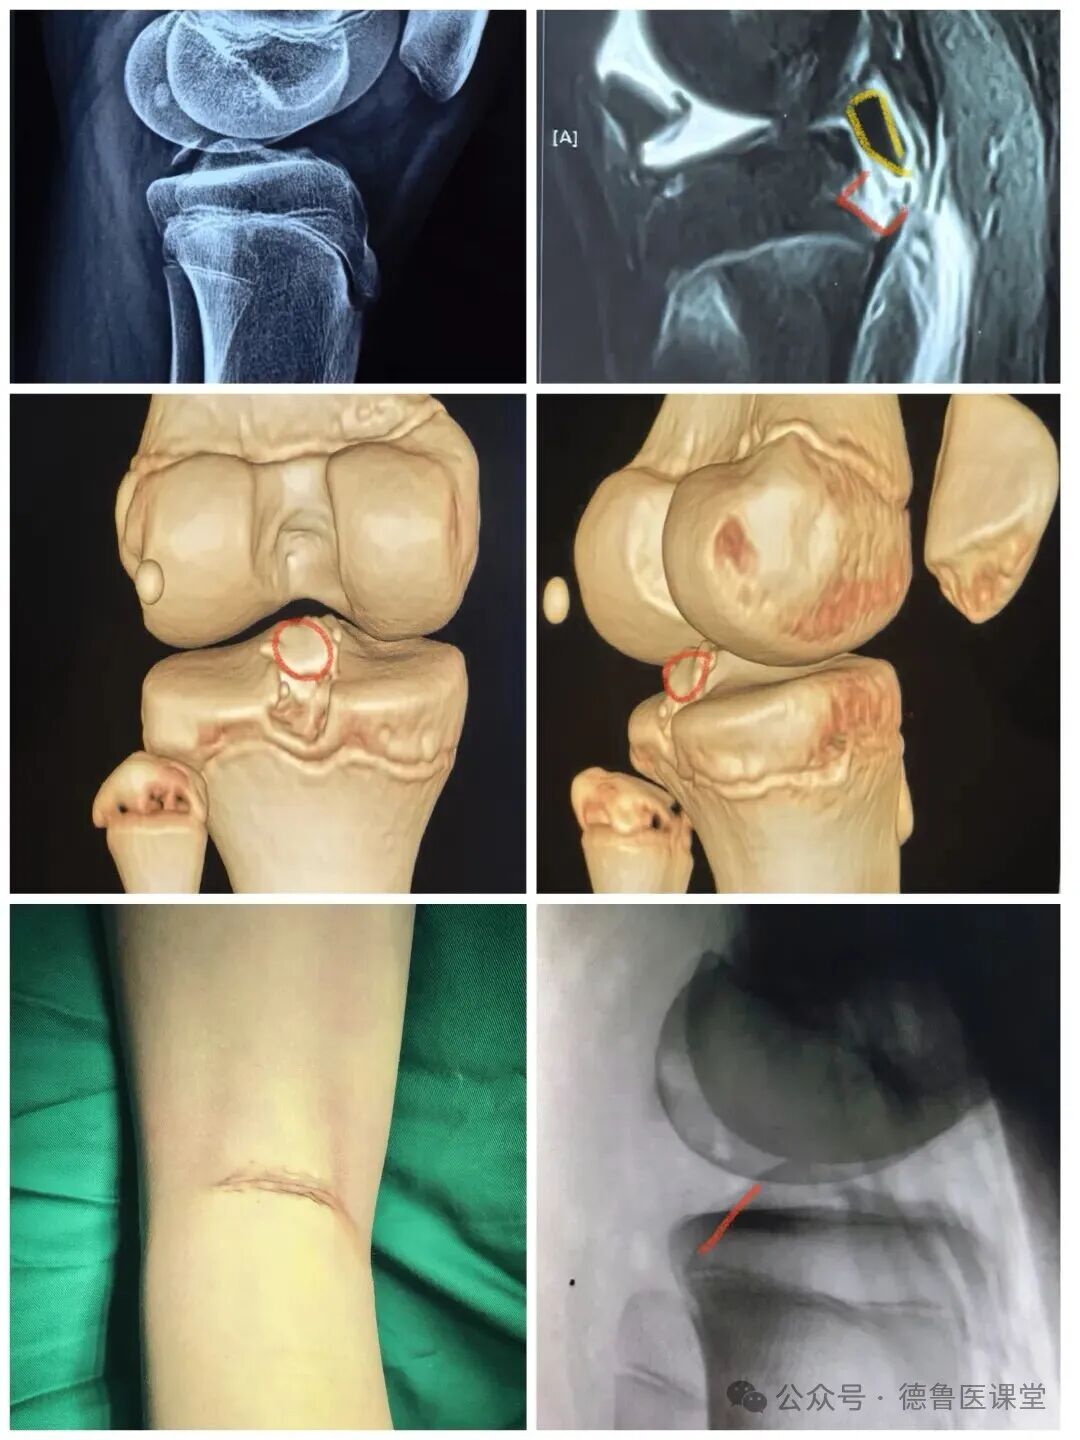

后叉止点撕脱骨折

Ⅲ型 完全移位

查体不稳

在腘横纹切

疤痕最不明显

对膝关节功能影响最小

术后直接可调式支具固定

逐步指导康复锻炼